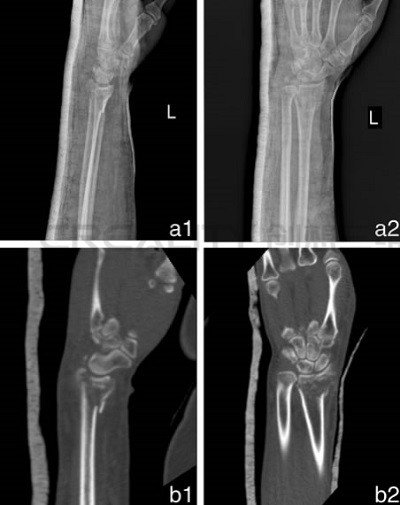

3D打印機(jī)制造模型如何改善骨折治療

中國(guó)研究人員正在研究使用3D打印機(jī)制造模型來改善骨折治療。第二附屬醫(yī)院骨科和浙江溫州醫(yī)科大學(xué)育英兒童醫(yī)院的華晨在“使用3D打印機(jī)制造的模型來改善骨折治療功效&rd...